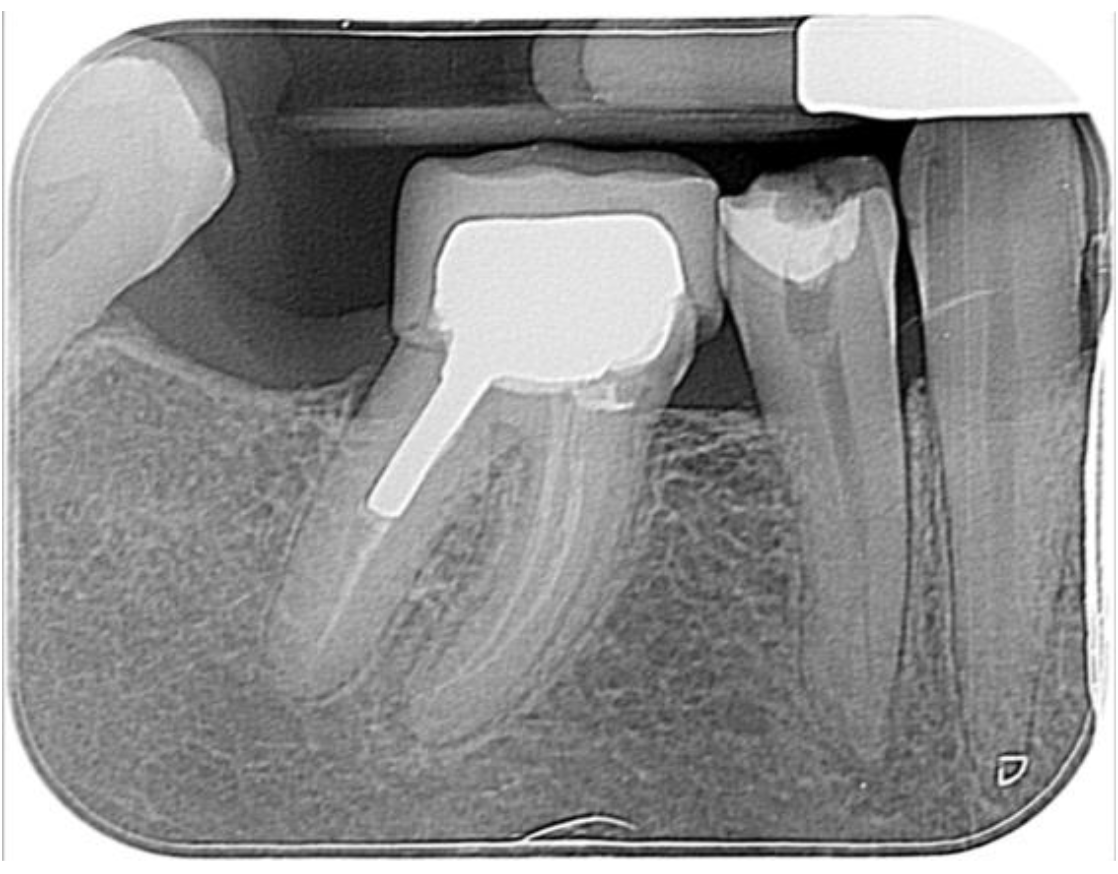

This Vertucci type V LR4 case had been previously initiated by the referring dentist (RD) and displayed minimal apical change on the pre-op IOPA.

Once I had carried out a consultation and taken my own IOPAs, including a mesial angle shift, I felt the root treatment had an excellent chance of success for this tooth. Usual local anaesthetic rubber/liquid dam protocols were used. The tooth was reaccessed using a combination of ultrasonic access tips and LG burs to improve straight-line access to the deep-lying apical split. Preparation was completed using Dentsply’s Reciproc Blue R25 file using lengths calculated from the Morita ZX apex locator (zero readings -0.5mm). Copious irrigation was performed with 5.25% NaOCl and 17% liquid EDTA.

All irrigants were activated using passive ultrasonic irrigation (PUI) with Eighteeth’s Ultra X. It was then filled using a combination of warm vertical compaction (WVC) and AH+ resin-based sealer. 3M’s Filtek’s bulk one resin was used as a nayyar core. This lovely lady was then returned to her RD to provide cuspal coverage.